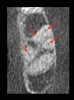

A CBCT scan was performed, and the findings revealed a lesion extending into the sinus cavity (Figure 7). The entire left maxillary sinus cavity was completely flooded with the lesion extending to the ostium, preventing proper drainage.

Figure 6 and Figure 7. Radiograph and CBCT scan shows a completely obstructed sinus cavity stemming from pathology associated with a failing upper left premolar.

Figure 7